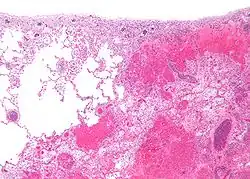

Infarctul (lat. infarctus) reprezintă moartea brutală și masivă a celulelor țesutului (necroză ireversibilă a unei părți a unui organ) cauzată de lipsa locală a oxigenului, din cauza unei obstrucții a arterei țesutului.[1] Procesul de formare a unui infarct se numește infarctizare, iar rezecția unui infarct se numește infarctectomie.[2]

Alte tipurie de infarct sunt infarctul cerebral(en)[traduceți], infarctul pulmonar, infarctul intestinal, infarctul placentar, infarct de splină(en)[traduceți], infarct al membrului(en)[traduceți] (braț sau picior), infarct al osului, al testiculului și al ochiului.